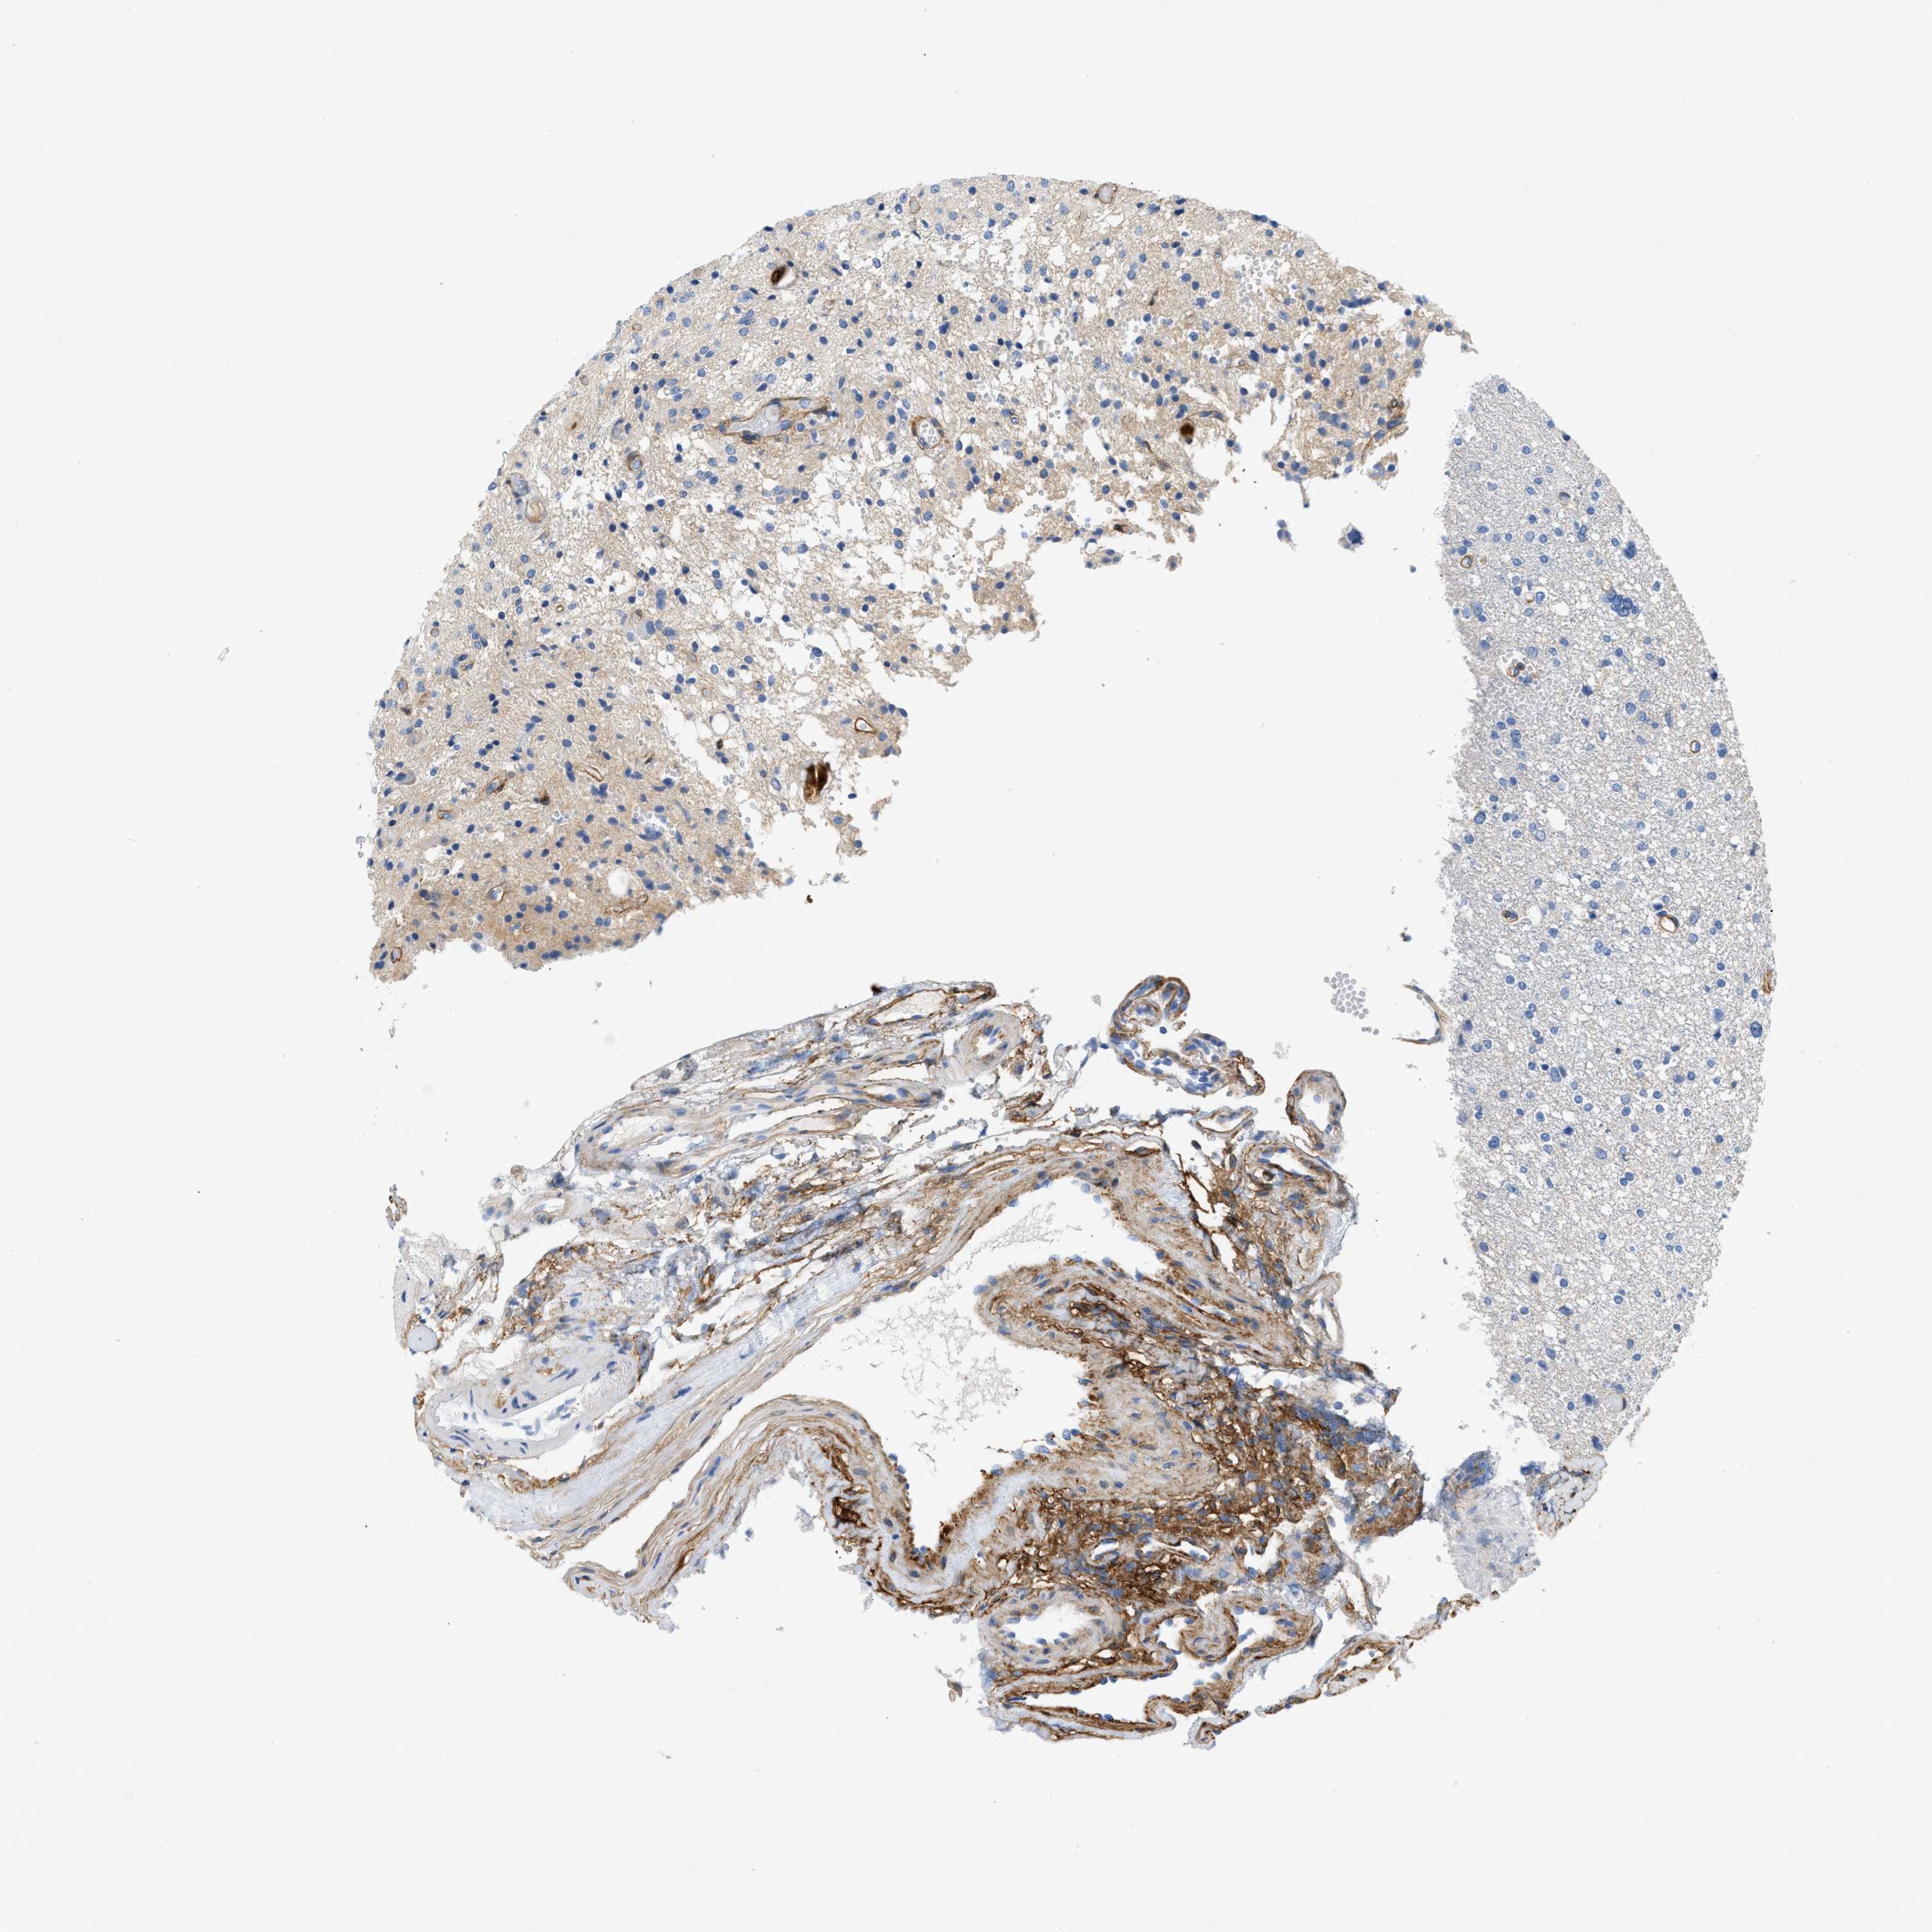

GLIOMA - Protein expressioni

A mouse-over function shows sample information and annotation data. Click on an image to view it in a full screen mode. Samples can be filtered based on level of antibody staining by selecting one or several of the following categories: high, medium, low and not detected. The assay and annotation is described here.

Note that samples used for immunohistochemistry by the Human Protein Atlas do not correspond to samples in the TCGA dataset.

Antibody stainingi

Antibody staining in the annotated cell types in the current human tissue is reported as not detected, low, medium, or high, based on conventional immunohistochemistry profiling in selected tissues. This score is based on the combination of the staining intensity and fraction of stained cells.

Each image is clickable and will lead to virtual microscopy that enables deeper exploration of all samples and also displays staining intensity scores, fraction scores and subcellular localization as well as patient and tissue information for each sample.

Antibody CAB003842

Antibody CAB018144

Staining

High

Medium

Low

Not detected

Intensity

Strong

Moderate

Weak

Negative

Quantity

>75%

75%-25%

<25%

None

Location

Nuclear

Cytoplasmic/membranous

Cytoplasmic/membranous,nuclear

Glioma, malignant, High grade

Glioma, malignant, NOS

Glioma, malignant, Low grade